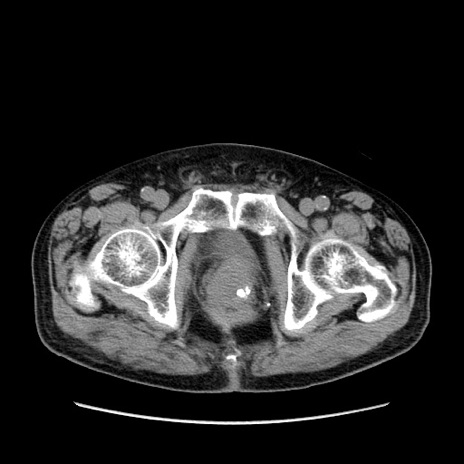

症例24(横断像)

【症例】80歳代男性

【主訴】左側腹部痛、嘔吐

【現病歴】本日早朝より左腹部に痛みあり。昼頃嘔吐認めたため、救急要請。

【既往歴】直腸癌(Mile手術)、胆摘

【身体所見】意識清明、BT 35.9℃、BP 221/93mmHg、SpO2 97%(RA) 、腹部:左ストーマ周囲に限局性の腹部膨隆あり。 膨隆部自発痛・圧痛あり・軟。

【データ】WBC 7700、CRP 0.09